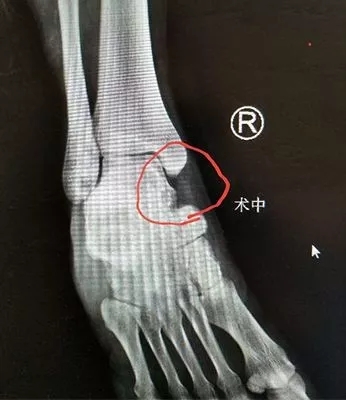

在求治多家医院后,本周一上午小朱来到必威官方首页官网betway足踝外科专家门诊,当时正是业务院长石荣剑坐诊,经过询问病史、体检和X光、CT三维重建,石院长发现患者脚里跟骨和距骨间长出来了一个像桥一样的高密度影,最终诊断是少见的跟距骨桥。

4月24日上午,石院长在手术室为小朱做了骨桥微创切除,先是以骨桥最突出点为中心做内踝下长约2厘米弧形切口,之后逐层分离保护血管神经束,再用微形摆锯按术前设计方案将骨桥切除,整个手术仅用了20多分钟就结束,术后患者恢复良好,当日就已下地行走。

术中